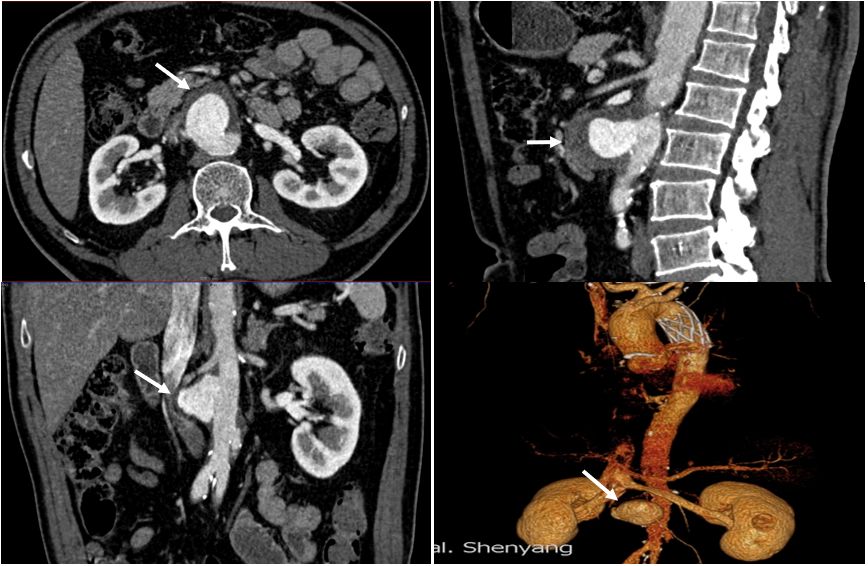

箭头所指:肾动脉领域腹主动脉瘤